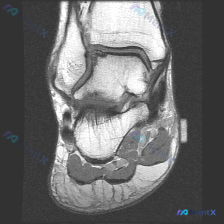

给大家分享一份最近遇到的踝关节MRI读片病例,初始问题指向软骨异常,整理一下完整的分析思路,一起讨论。 一、病例影像基本信息 这是一份踝关节矢状位T2加权MRI图像,图像质量好,信噪比高,解剖结构清晰,涵盖了胫骨远端、距骨、跟骨、足舟骨、骰骨及部分跖骨基底部,胫距关节、距下关节、窦跗管、跟腱等关键结...

看到这个踝关节MRI的读片讨论,整理了完整的影像信息和分析思路,分享给大家。 一、影像基本信息 这是一张踝关节MRI矢状位T2加权图像,T2序列对液体和软组织水肿显示敏感,以下是具体异常发现: 1. 距下关节及跗骨窦区域:距骨下方、跟骨上方的关节间隙及周围软组织可见弥漫性高信号,提示明显积液或炎性水...

刚看到一份踝关节MRI病例,问题是询问影像上观察到的软骨异常相关发现,整理一下资料和分析思路分享给大家。 病例影像基础信息 这是放射影像-踝关节MRI-T2序列-矢状位,系统评估整体结构如下: 1. 骨与关节:胫距关节间隙正常,关节面轮廓可,距骨穹窿皮质连续,未见明确骨折线或弥漫骨髓水肿;距下关节、...

最近碰到一个很有启发的病例,临床问题是问这张踝关节MRI-T1矢状位影像的观察结果是不是软骨异常,整理一下完整分析思路给大家。 一、影像基本信息 本次仅提供踝关节MRI-T1序列-矢状位单张图像,先把客观阅片结果整理出来: 1. 骨骼结构:胫骨远端、距骨、跟骨、足舟骨及部分楔骨显示清晰,骨皮质连续,...